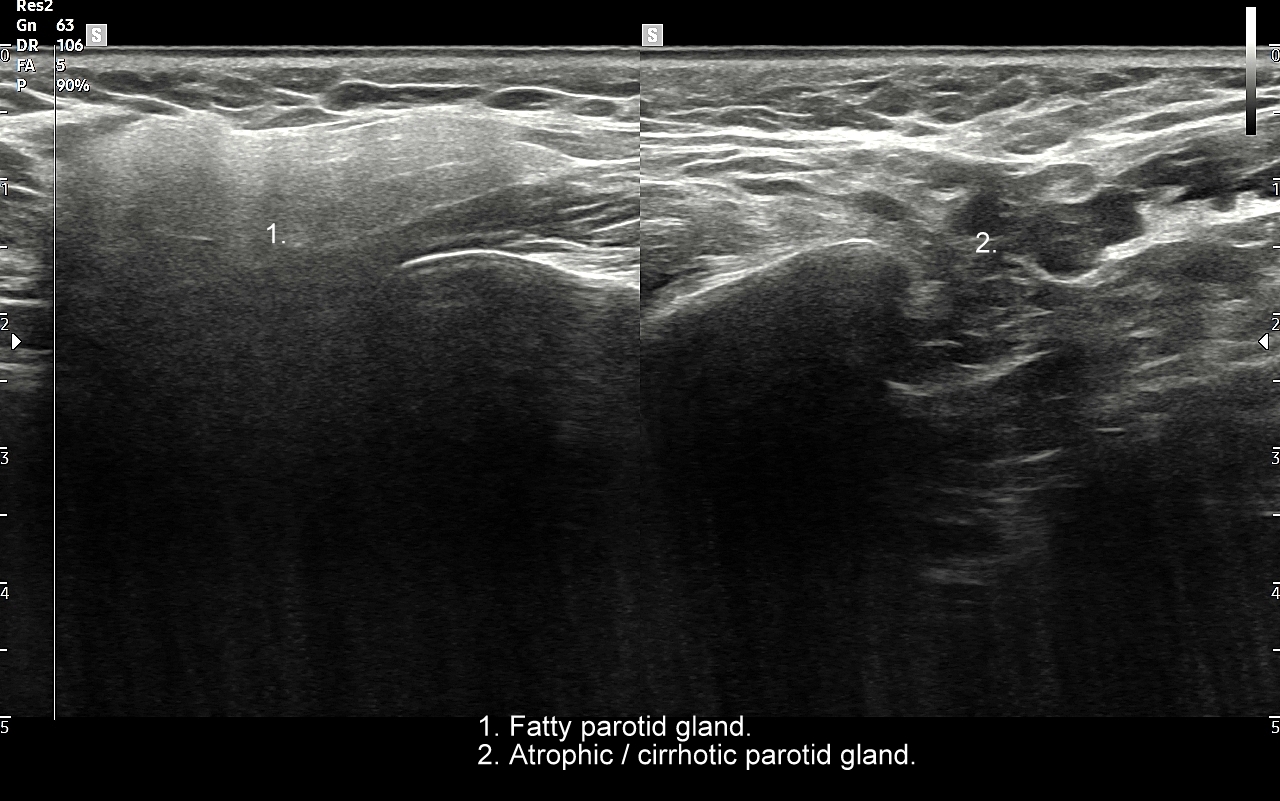

Ślinianki podlegają różnorodnym procesom chorobowym. Ostre stany zapalne wystąpić mogą w przebiegu infekcji wirusowych, których przykładem jest infekcja wirusem świnki (syn. nagminne zapalenie przyusznic). Z kolei przykładem zapalenia przewlekłego jest zespół suchości ust, czyli zespół Sjögrena. Stosunkowo częstym schorzeniem dotykającym ślinianki jest kamica (ang. sialolithiasis). W jej przebiegu dochodzić może do zablokowania odpływu śliny, obrzęku gruczołu, wystąpienia bólu, a nawet wtórnego zapalenia i zakażenia bakteryjnego. W śliniankach występować mogą również guzy nienowotworowe oraz guzy nowotworowe.

Przykładami guzów nienowotworowych w śliniankach są odczynowe węzły chłonne i torbiele. Najczęstszymi nowotworami łagodnymi są gruczolak wielopostaciowy, zwany także guzem mieszanym (tzw. tumor mixtus) oraz gruczolak limfatyczny (tzw. guz Warthina) posiadający sonograficzne cechy nowotworu lito-torbielowatego. Guz mieszany jest zmianą wolno rosnącą z tendencją do miejscowej wznowy po zabiegu chirurgicznej resekcji. Z kolei guz limfatyczny, czyli guz Warthina, częściej występuje u palaczy papierosów, może być obustronny, a ze względu na swój histologiczny charakter może pojawić się po przebyciu infekcji górnych dróg oddechowych. Wśród nowotworów złośliwych dominują rak śluzowo-naskórkowy, gruczołowo-torbielowaty i gruczolakorak. Nowotwory ślinianek najczęściej umiejscawiają się w śliniance przyusznej, a większość z nich ma charakter łagodny. W przypadku nowotworów lokalizujących się w pozostałych śliniankach częściej spotyka się guzy złośliwe.

Pacjenci ze skierowaniem na badanie USG ślinianek zgłaszają się do Pracowni zwykle w przypadku dolegliwości subiektywnych bądź obiektywnych zlokalizowanych w okolicy żuchwy i górnych partii szyi. Należy jednakże mieć na uwadze, że patologie umiejscowione w wymienionych obszarach nie zawsze odpowiadają chorobom ślinianek, a mogą dotyczyć np. węzłów chłonnych, migdałków, czy innych tkanek miękkich szyi. USG to podstawowe badanie obrazowe ślinianek. Jest procedurą bezpieczną i dokładną, a w Pracowni dr Szczepańskiego ślinianki oceniane są nowoczesną metodą MPUS (multiparametryczne USG) z zastosowaniem trybów mikrounaczynienia i elastografii. W przypadku konieczności oceny głębokich części ślinianek przyusznych albo zaplanowania operacji w obrębie szyi wykonuje się tomografię komputerową lub rezonans magnetyczny szyi.